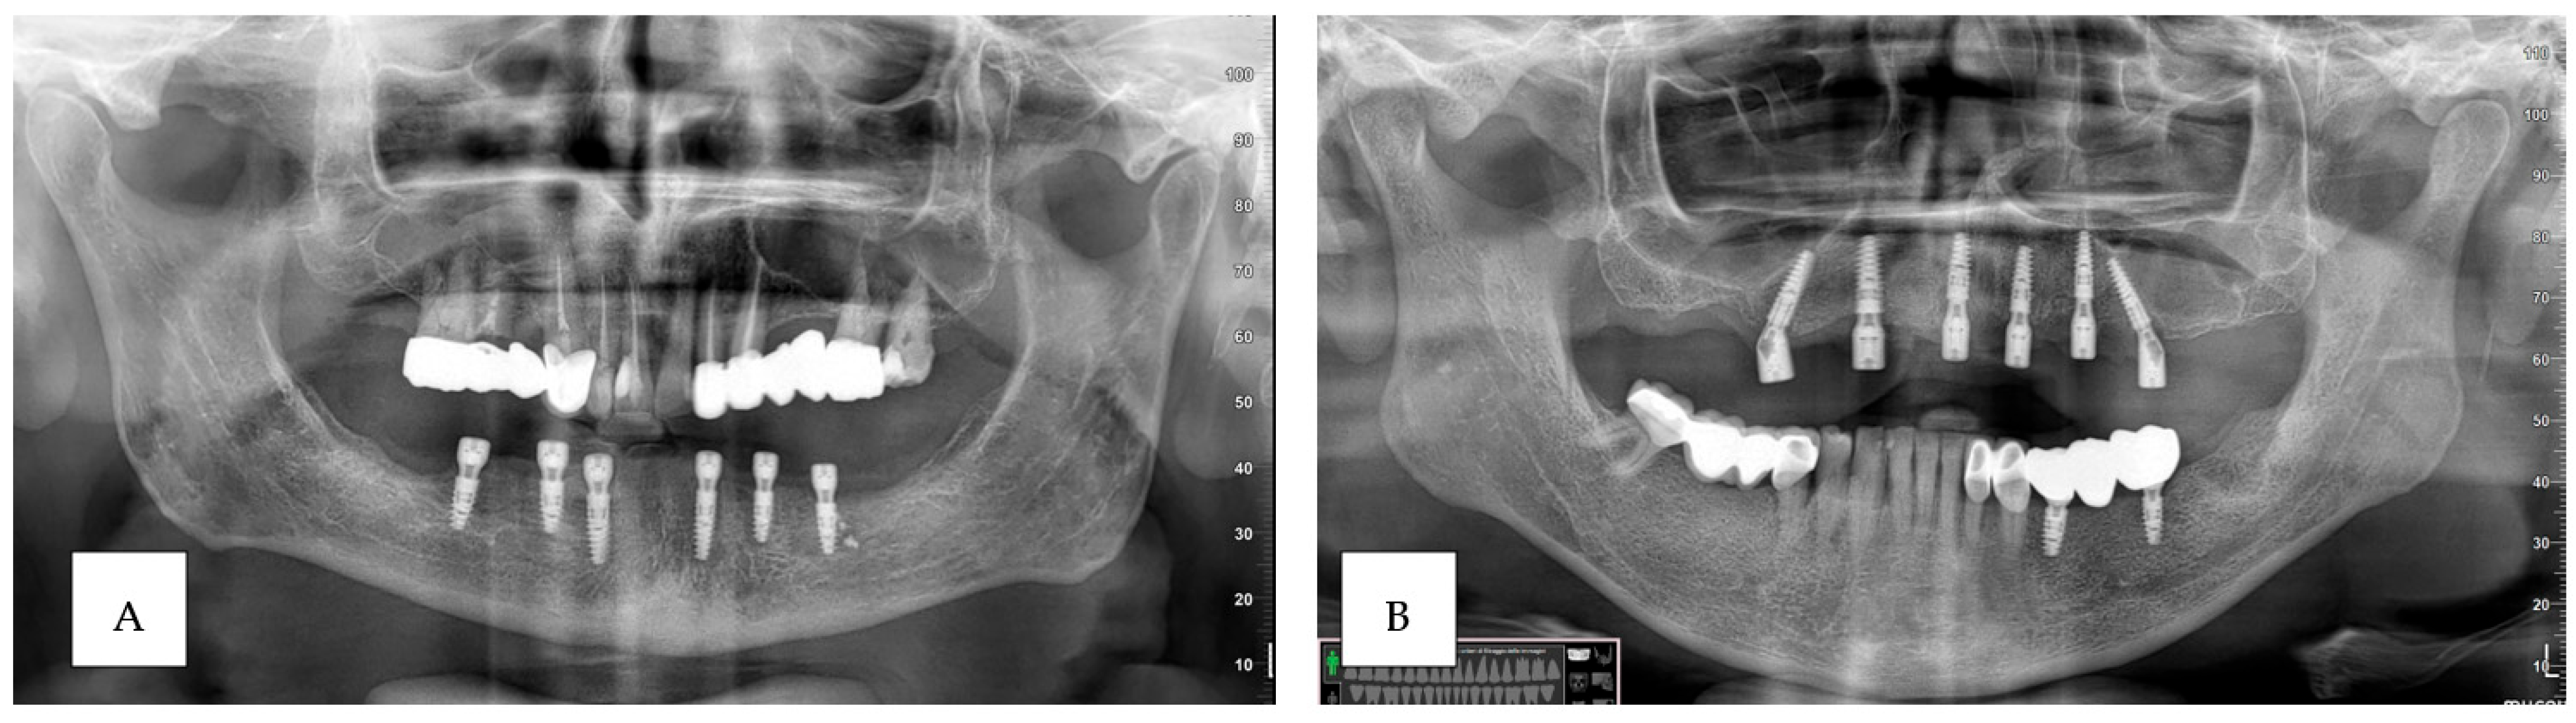

2. Materials and Methods

2.3. Surgical Procedure

3. Results